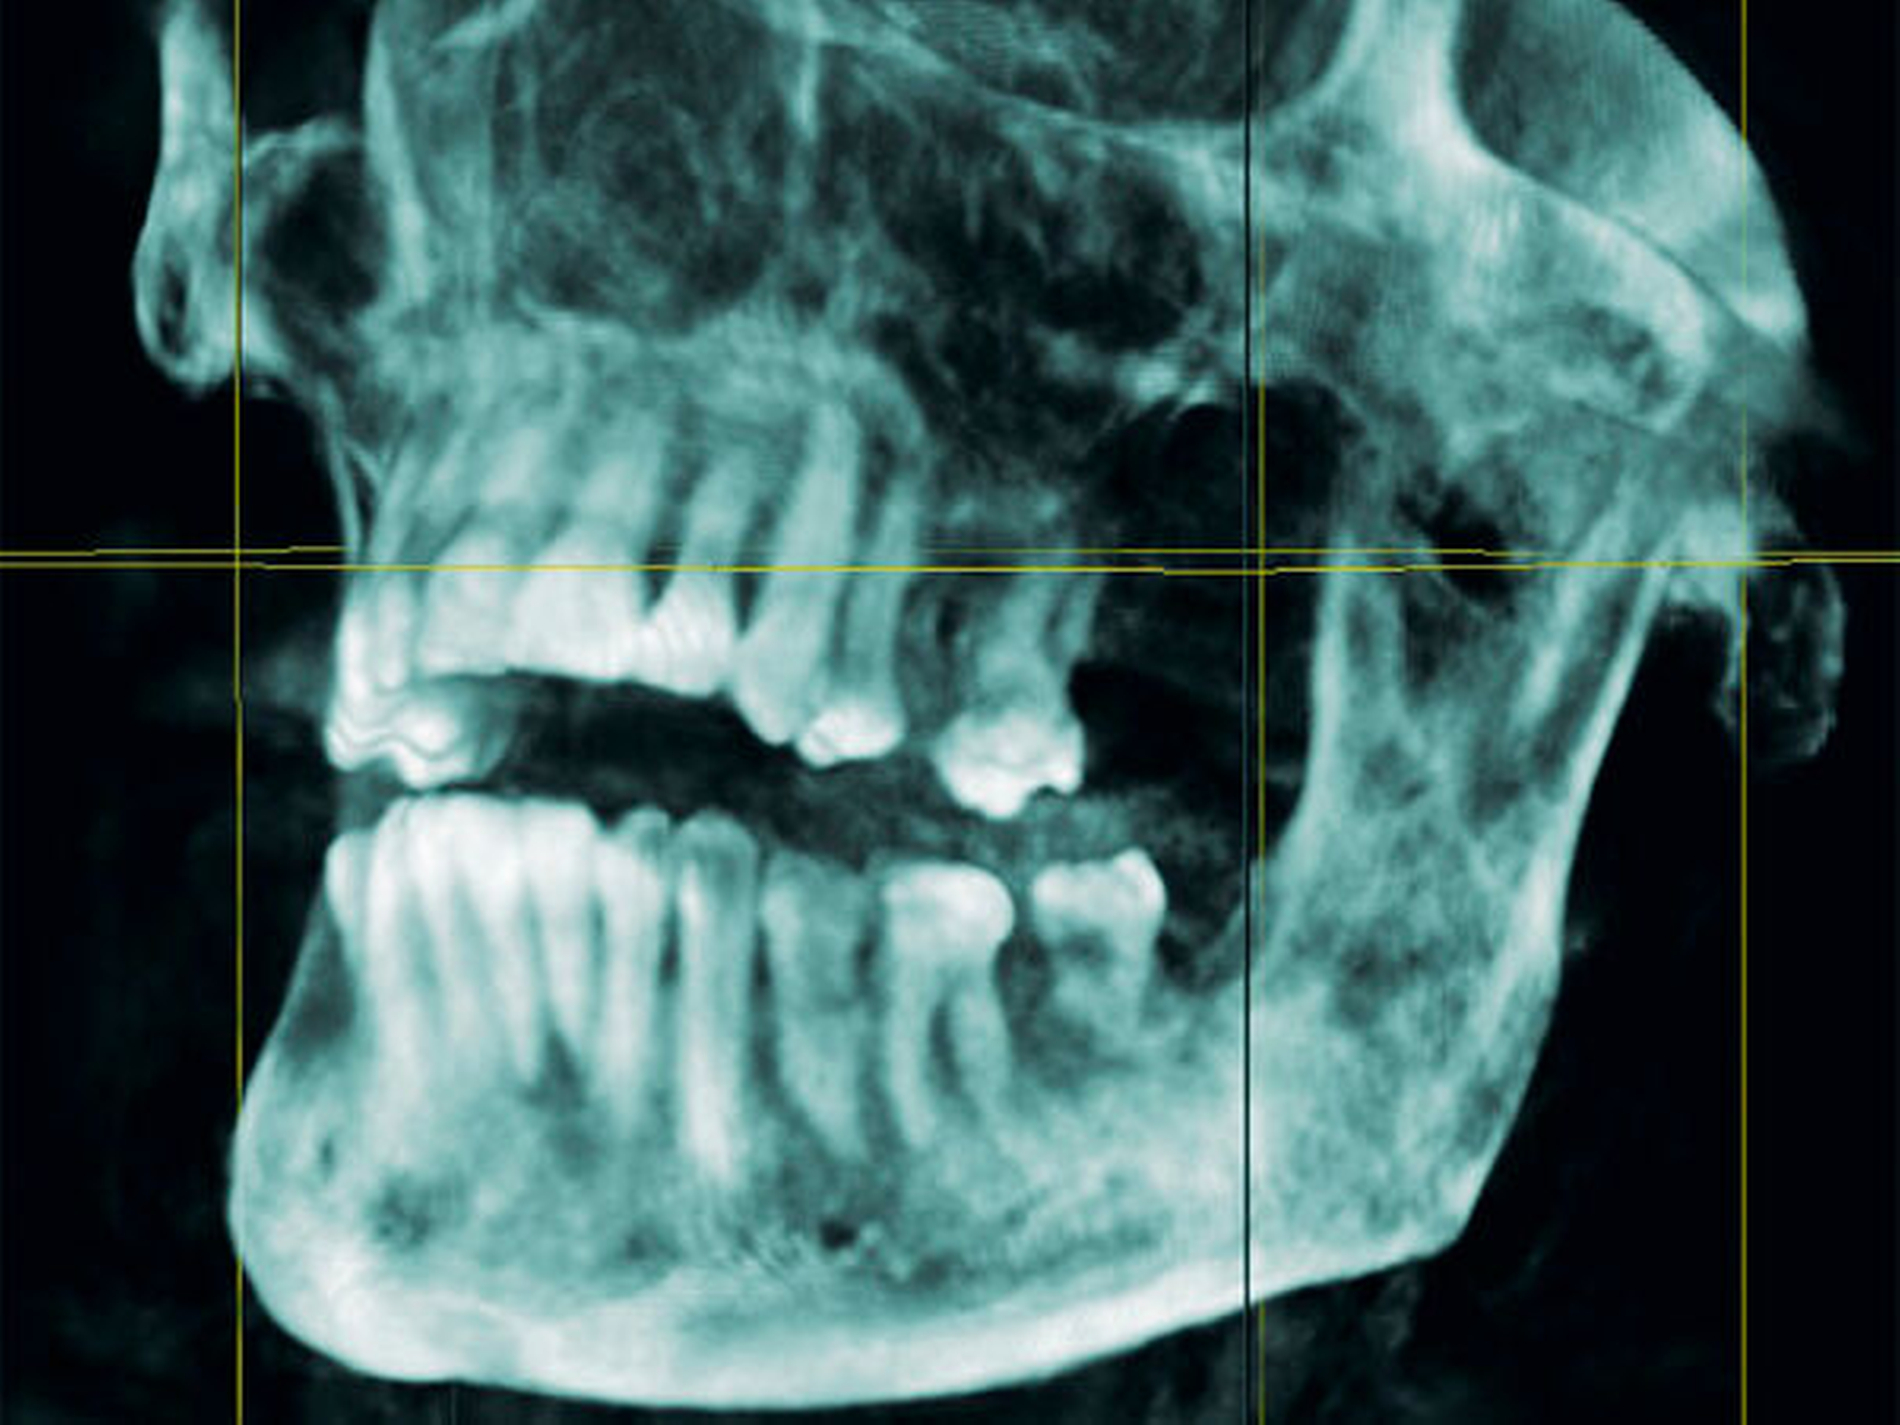

Zum Ausschluss einer Mittelgesichtsfraktur bei palpatorischem Weichteilemphysem erfolgte zur weiteren Diagnostik eine DVT-Aufnahme. Es zeigten sich keine Frakturen im Bereich des Mittelgesichts oder der Kiefer. Jedoch kam in der DVT-Bildgebung sowie in der OPT-Optik ein massives Weichgewebeemphysem zur Darstellung (Abbildungen 2 bis 5).

Weiterhin wird deutlich, dass bei in aller Regel doch sehr eingeschränkter Beurteilbarkeit von Weichgewebe im DVT in diesem speziellen Fall eine weiterführende Diagnostik und Therapie eingeleitet werden konnte.

Das Emphysem war initial im DVT so eindrucksvoll sichtbar, dass es trotz fehlender klinischer Symptomatik im Thoraxbereich, schwieriger Anamnese und blander zweidimensionaler Bildgebung der Lunge (RÖ-Thorax) der Faktor für eine weitere dreidimensionale Bildgebung (CT-Thorax) war, die letztendlich die Verdachtsdiagnose sicherte.

Zur Frakturdiagnostik im Mittelgesichtsbereich eignet sich das DVT sehr gut, außerdem ist die freie Luft des Emphysems im undifferenzierten Weichgewebe gut darstellbar.

Mittels der digitalen Volumentomografie können Weichteile schlecht bis gar nicht beurteilt werden, Lufteinschlüsse im Weichgewebe hingegen können gut dargestellt werden.